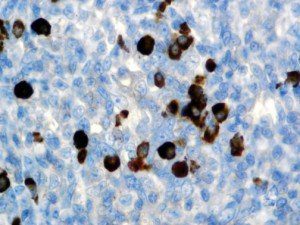

It is the ICU physician who is most likely to witness one of the deadliest manifestations of the abnormal immunological response, the cytokine storm syndrome (CSS). This response is also referred to by some as the cytokine release syndrome (CRS). CSS is characterized by continuous activation and expansion of macrophage and lymphocyte populations, which secrete large amounts of cytokines, causing the cytokine storm. This massive cytokine release is akin to hemophagocytic lymphohistiocytosis (HLH) disease, a syndrome characterized by initial unchecked and persistent activation of cytotoxic T lymphocytes and NK cells.

Clinical and laboratory manifestations of HLH include fever, enlarged liver and/or spleen, neurologic dysfunction, coagulopathy, liver dysfunction, cytopenias (i.e., low levels of erythrocytes, leukocytes, and/or platelets), hypertriglyceridemia, hyperferritinemia, hemophagocytosis, and eventually diminished NK cell activity as the immune system becomes progressively paralyzed. HLH can be familial (primary HLH) or secondary to another disease process (sHLH), such as rheumatic disease, in which it is referred to as macrophage activation syndrome (MAS, characterized by elevated ferritin).